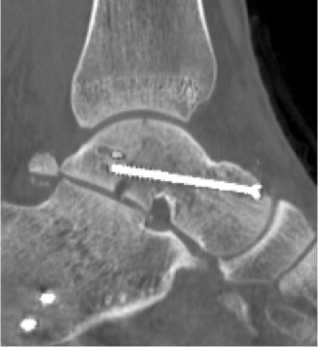

После повторной КТ пациент был вновь поднят в операционную. Дальнейшая тактика лечения заключалась в выполнении дополнительного, переднемедиального, доступа к таранной кости, переднелатеральный доступ также использовался. Манипулируя отломками из двух доступов достаточно легко удалось устранить смещение таранной кости и осуществить репозицию отломков в нормальное положение. В последующем под ЭОП-контролем был проведён остеосинтез перелома таранной кости двумя канюлированными спонгиозными винтами с неполной резьбой, проведёнными из головки через шейку в блок таранной кости. Выполнялось послойное ушивание ран, восстановление нижнего удерживателя сухожилий разгибателей пальцев стопы. В связи с тем, что пациенту уже был наложен АНФ «голень-стопа», принято решение о сохранении иммобилизации в послеоперационном периоде в аппарате. На итоговой контрольной КТ: вывих таранной кости устранён, блок таранной кости восстановлен, положение отломков и фиксаторов корректное, но был обнаружен костный дефект таранной кости, переходящий на подтаранный сустав (рис. 3). Послеоперационный период протекал без особенностей, и пациент был выписан на амбулаторное долечивание на третьи сутки.

Рисунок 3. Компьютерная томография после вправления вывиха и остеосинтеза таранной кости: A – фронтальный срез;

B – аксиальный срез; C – сагиттальный срез

Figure 3. Computed tomography after reduction and osteosynthesis of the talus: A – frontal view; B – axial section; C – sagittal section